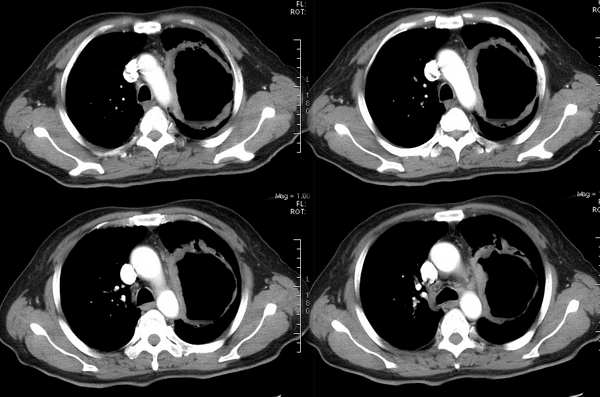

病例一,男,58岁,胸痛半月余

病例二,男,63岁,咳嗽、低热月余。

②ct249:由gaozhengyi版主提供

http://www.radida.com/radinet/read.php?tid=654&page=1

患者女,65岁,主因低热、咳嗽、痰中带血丝一周多来院。

继续抗炎治疗后复查病变进一步缩小。可惜未留下图片。但抗炎前后的片子对比已能证实为炎性病变。

③35岁女性,因颈部包块术前检查发现右下肺圆形结节。

④男性,65岁,咳嗽、咳痰3月。

⑤男性,45岁,咳痰,痰中带血。

⑥男性,45岁。一个月前开始咳嗽。

⑦女性36y,胸痛2周住院。 手术后病理为:炎性假瘤。

⑧患者,男,48岁,于2001年因“反复声嘶9个月”在外院确诊为喉鳞状上皮癌,行手术切除。10天前患者无明显诱因出现左侧背部疼痛,进行性加重,患者无咳嗽、咳痰、发热。

实验室检查:ce125:128uml ly:0. 6x109/l wbc:10.1x109/l ne:8.3x109/l

左上肺炎性假瘤:

细支气管上皮增生、纤维母细胞增生及纤维化,间质有炎细胞浸润及淋巴滤泡形成,边缘有坏死组织。

⑨男,52岁,痰中带血两天。无明显发热,化验室检查正常。

⑩女,58岁。无不适,体检发现胸部肿物,行ct检查。

(11)女30岁,查体发现右肺上叶肿块